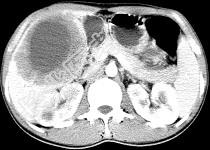

单项选择题女,61岁, 上腹部疼痛一个月,食欲减退, 消瘦,CT所见如图, 最可能的诊断是 ( )

A、肝脓肿

B、肝转移瘤

C、胃癌肝转移

D、肝包虫病

E、原发性肝癌